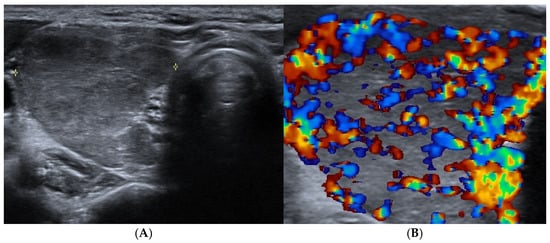

4. Thyroid Nodules

4.1. How to Assess a Clinically Relevant Thyroid Nodule: The Role of Ultrasound